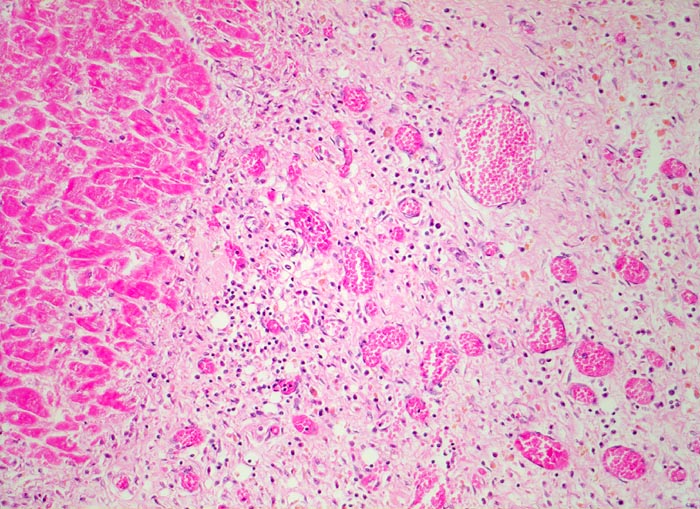

PathoPic – image database / PathoPic ID 4820 - subakuter Myokardinfarkt

subakuter Myokardinfarkt

Das Granulationsgewebe rechts im Bild besteht aus lockerem Bindegewebe, Kapillaren und gemischtem Entzündungsinfiltrat. Die hämosiderinhaltigen Makrophagen sind an ihrer gelben Farbe erkennbar. Links im Bild die Koagulationsnekrose mit schollig zerfallenen hypereosinophilen Myokardfasern.

Ausgedehnter subakuter Myokardinfarkt von Hinterwand und Septum. Im Infarktrandbereich perakute Myokardnekrosen.

Narbengewebe kann ebenfalls vaskularisiert sein. Für die Diagnose eines subakuten Infarktes muss das Granulationsgewebe auch Entzündungszellen enthalten.